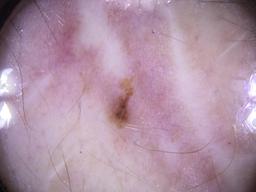

ISIC_8336318

Clinical

| Field | Value |

|---|---|

| age_approx | 40 |

| anatom_site_1 | Trunk |

| anatom_site_2 | Anterior trunk |

| anatom_site_3 | Anterior abdomen |

| clin_size_long_diam_mm | 6.19 |

| diagnosis_1 | Malignant |

| diagnosis_2 | Malignant melanocytic proliferations (Melanoma) |

| diagnosis_3 | Melanoma Invasive |

| diagnosis_4 | Melanoma Invasive, Superficial spreading |

| diagnosis_confirm_type | histopathology |

| image_manipulation | instrument only |

| image_type | TBP tile: close-up |

| lesion_id | IL_5097969 |

| mel_thick_mm | 0.40 |

| patient_id | IP_8989787 |

| sex | male |

| tbp_tile_type | 3D: white |